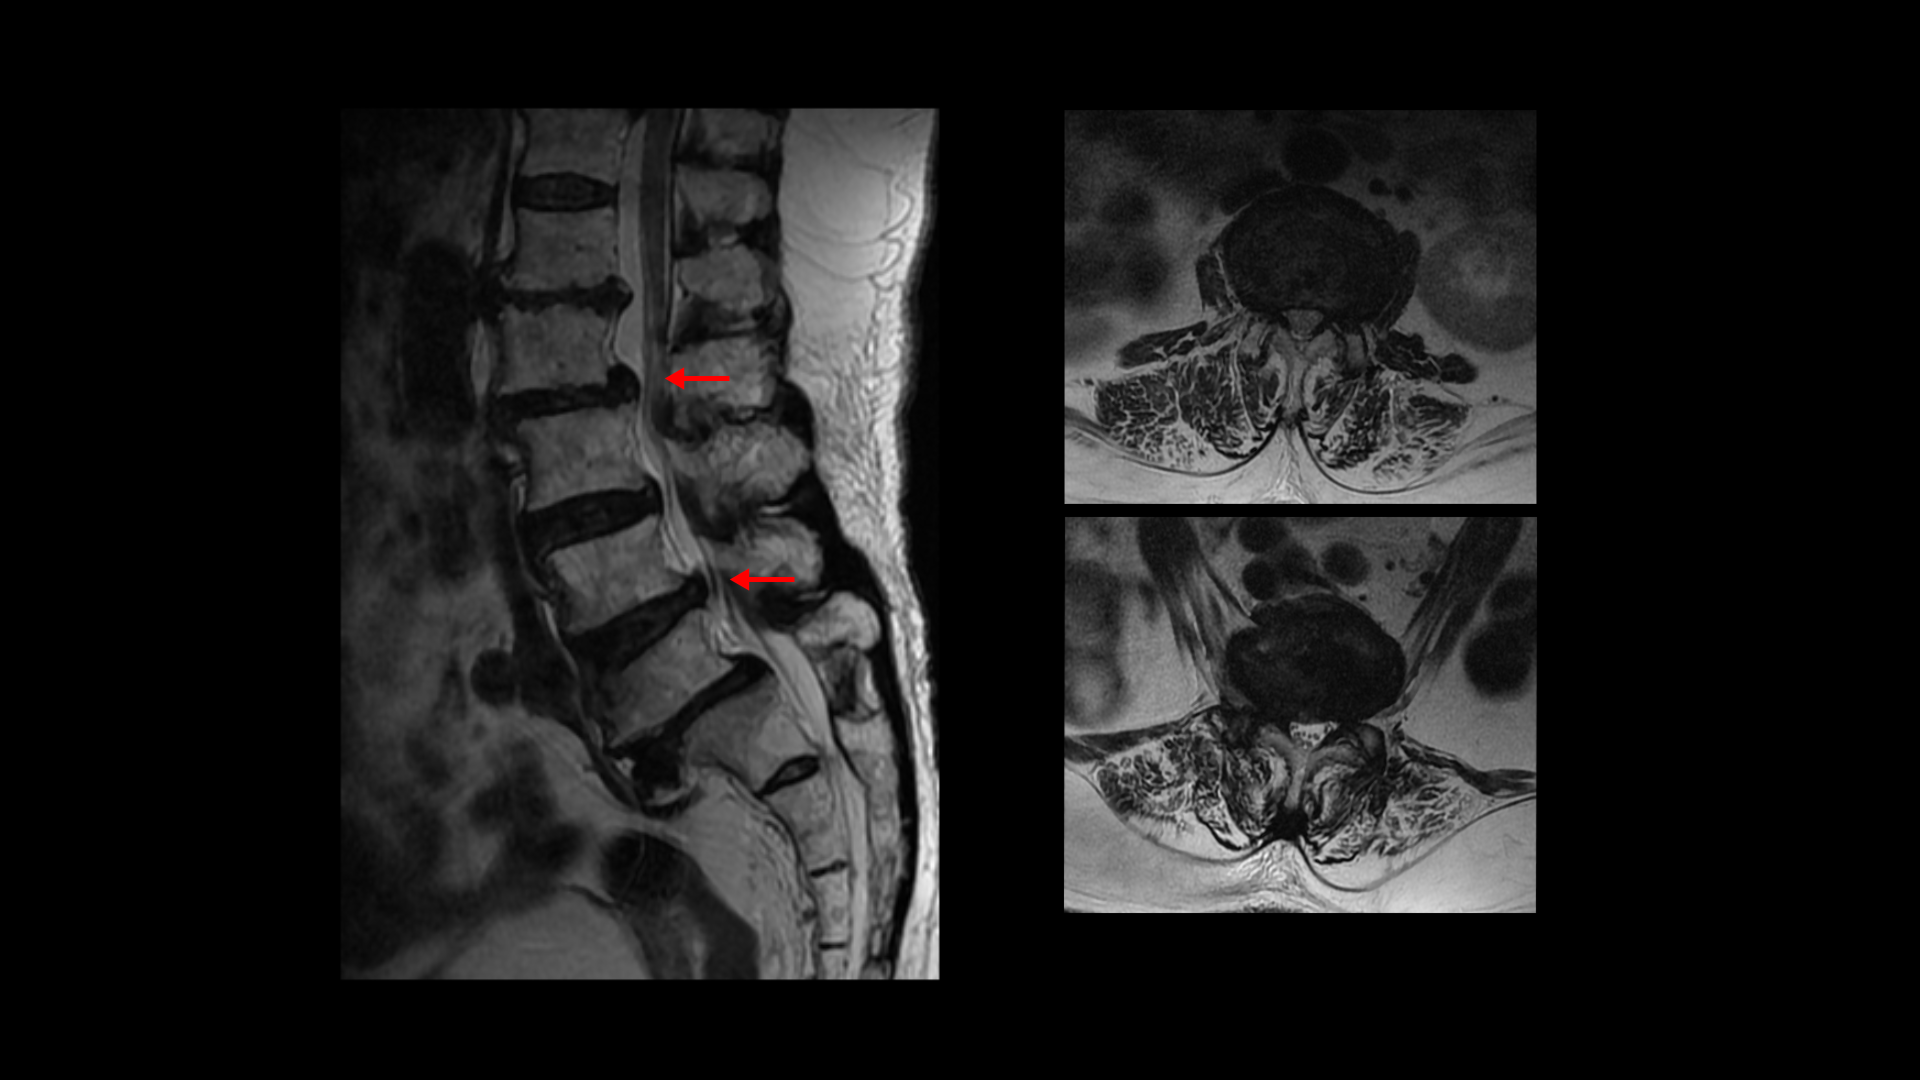

이분 MRI를 보면 보시다시피 허리의 5마디가 전부 퇴행이 진행되어 있습니다.

여러 마디 2번 3번, 4번 5번에 척추관협착이 있고

2번 3번, 4번 5번, 오른쪽 신경가지가 빠져나가는 구멍들이 다섯 마디 전부가 다 오른쪽 좁아져 있습니다.

그런데 이분은 허리도 굽으셨는데 척추근육, 특히 허리를 세워주는 기립근을 mri에서 보면 허리 다섯 마디 전체에서 기립근의 근육이 지방으로 변해서 하얗게 보이는 지방화가 심합니다.

이렇게 근육이 지방으로 심하게 변하고 기능이 떨어지면 허리를 펴기가 어렵고 허리가 아플 수 밖에 없습니다. 여기 건강한 기립근과 비교해서 보면 그 차이를 금방 알 수가 있습니다. 기립근 크기도 차이가 크고 하얗게 지방으로 변해버린 부분을 잘 보실 수 있습니다.